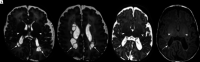

Fig 3.

PVL. T2-weighted images in the axial plane at the level of the basal ganglia (A) and the corona radiata (B) of an infant born at 29 + 5 weeks’ and imaged at 39 + 1 weeks’ PMA. There are cysts in the periventricular white matter bilaterally (arrows, A and B) accompanied by an absence of high-T1/low-T2 signal in the PLIC, denoting an absence of myelin (arrowheads, A). More commonly, cysts are not seen at term age. T2- (C) and T1-weighted (D) images in the axial plane at the level of the basal ganglia and PLIC in an infant born at 29 + 3 weeks’ and imaged at 40 + 2 weeks’ PMA show mild angulation and dilation of the posterior horns of the lateral ventricles and high-T1/low-T2 signal in the periventricular white matter (arrows, C and D), secondary to white matter volume loss (note that the sulci approximate the ventricular surface), similarly accompanied by a lack of myelin in the PLIC (arrowheads, C and D), features that are typical of noncystic PVL.